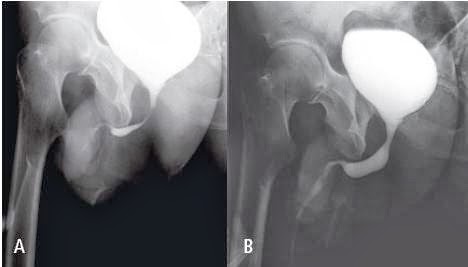

Fig. 10 - Vessie hyperactive. UCRM : (A) et (B) clichés rétrogrades

de remplissage.

(A) Aspect normal de l’urètre postérieur et du col vésical.

(B) Toujours pendant la phase rétrograde, chez le même patient,

surviennent des contractions vésicales spontanées, alors

que la vessie est encore très peu remplie. L’aspect évoque une

hyperactivité vésicale. Noter la paroi vésicale de lutte, la dysectasie

du col avec la saillie du lobe médian. Noter aussi la

distension de l’ensemble de l’urètre d’aval, avec un refl ux

dans les glandes de Cowper et les glandes prostatiques, liée à

l’hyperpression dans un système clos (le ballonnet de la sonde

de remplissage est en place).